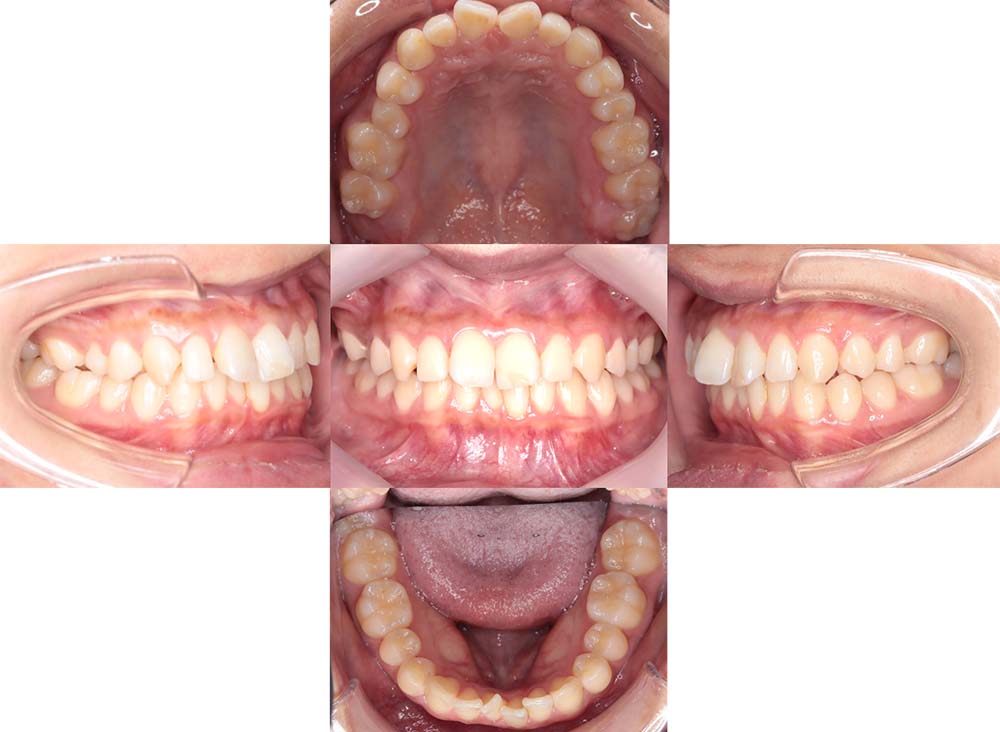

症例03

| 主訴 | 歯並びがガタガタしている。 |

| 診断名あるいは主な症状 | 過蓋咬合、叢生 |

| 年齢/性別 | 26歳・女性 |

| 矯正ステージ | 大人の矯正治療 |

| 治療方法 |

ワイヤー矯正 歯科矯正用アンカースクリュー(3本) |

| 抜歯部位/抜歯有無 | 抜歯 |

| 治療内容 | 上下顎の奥歯を後方に移動後、ガタガタの改善と上下顎前歯を後退させた。 |

| 費用 |

90万円程度(2025.10時点の料金となります。) ※矯正基本料金、アンカースクリュー、審美ブラケットを含む |

| 治療期間 | 2年8ヶ月 |

| 主なリスク・副作用 | 痛み、歯根吸収、歯肉退縮、虫歯、後戻り |